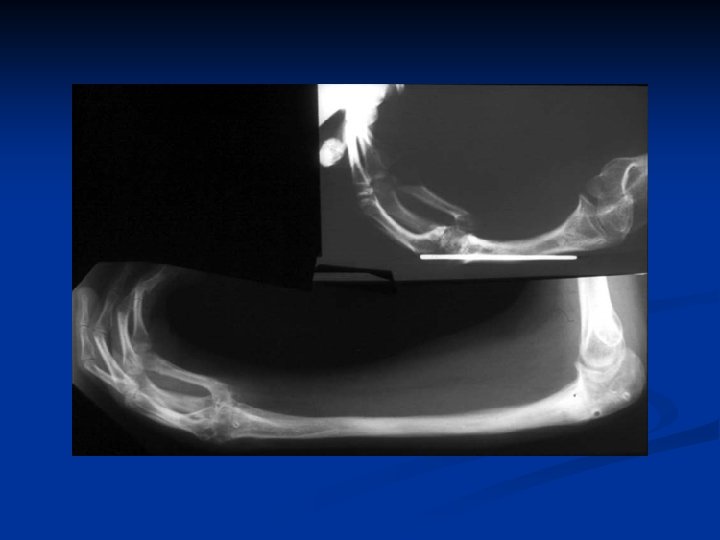

Distal Ulnar Osteotomy Reorient Original Ulno Carpal Psuedo Joint

16 y Radial clubhand 1 y centralization 2 y pollicization

12 Feb 03 Osteotomy R ulna + application TSF Intraop Post-op

During distraction

4 months post op.

Materials • 24 forearms • 20 patients

Range of Motion Decreased Same Increased 0 1 4

Complications Refractures 3 Premature Consolidation 1 Reoperation for Complications 2

Grip Strength Improved Worsened 24/24 0/24

Follow-up Mean Range 10 years 1 13 years

Lengthening Age (yr) Range (cm) Mean (cm) 6 9 10 14 5 8 8 10 7 9

Lengthening Once 24 Twice Total 6 28

Range of Motion • Finger flexion: increased range and grip strength in all patients • Finger extension: decreased MCP extension in 2 patients (20°) • Elbow extension: transient contracture in all patients, return to preop levels in all • Elbow flexion: improved in 2 and unaffected in 7

Lengthening Amount • Mean, 7. 6 cm • Range, 5 11 cm

Strategy This study Age 0 5 years: correction hand/pollicization 6 Age 6 10 years: 1 st stage lengthening 12 Age 11 -16 years: 2 nd stage lengthening 6 Age 11 20 years: one lengthening 6

Additional Deformity Correction • Distal ulnar osteotomy for hand angular realignment • Mid ulnar osteotomy for correction of ulnar bow • Bilaterals: Supination of forearm at end of lengthening for perineal care